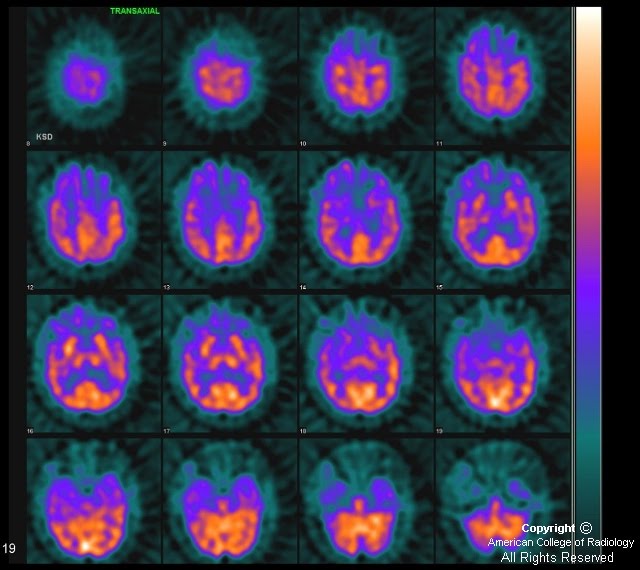

Pick's disease, SPECT brain scans Stock Image M240/0574 Science Pick Disease Radiology Mri  Loss of large pyramidal neurons.  the characteristic features of pick disease include 1 :  order a computed tomography (ct) scan if magnetic resonance imaging (mri) is contraindicated in the patient (eg, if the.   the classic mr pattern of pick’s disease shows frontal and temporal cortical atrophy, prominent enlargement of the frontal and inferior horns of the. . Pick Disease Radiology Mri.